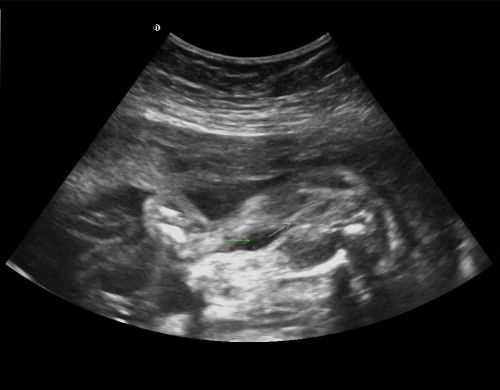

Sapa² ada pengalaman kena induce tak? Saya ada gdm, sekarang kandungan 38minggu 5hari...tapi baby kcik je.. Esok kena serah diri. Ada tak tips2 yg boleh korang kongsi selepas dimasukkan belon untuk cepatkan bukaan sebab sekarang pun masih takda tanda2 nk bersalin tanpa induce..#bantujawap#mohonbantujawabbunda #Needadvice #askmommies